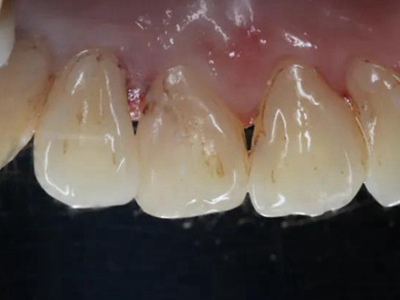

酸蚀症牙齿有黄斑轻微缺损图

酸蚀症症状较轻时,患者牙齿靠近牙根处有黄斑形成,有少量牙骨质缺损,出现较小的凹陷坑洼,该病多是长期接触外源性酸性物质或胃液反流导致。

酸蚀症牙齿根部有白斑及黄斑图

酸蚀症可表现为牙齿根部有白垩状斑片,形态不规则,还可有偏茶褐色的黄斑。因牙根暴露较多,部分牙齿有轻微凹陷,需少进食酸性食物。

酸蚀症牙齿根部有黄斑图

酸蚀症可使牙齿出现黄斑,境界不清,面积不大,主要分布于牙齿根部及牙缝处,呈淡黄色,牙齿尚未出现明显的骨质缺损,需减少进食酸性食物。

酸蚀症牙齿有黄斑牙龈萎缩图

酸蚀症患者的牙齿根部会有黄斑形成,边界模糊,周围有少量白斑,牙龈萎缩发白,露出牙根部。需控制致病因素,避免牙齿长期接触酸性物质。